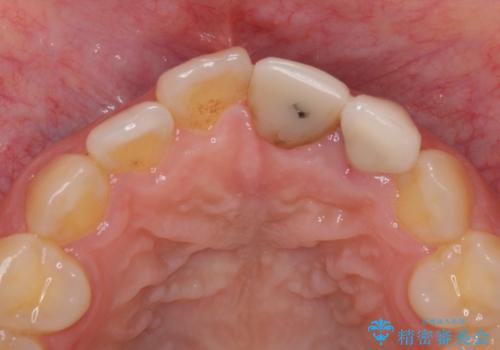

既にクラウンが装着されていた歯は歯根の先端に病変が認められたため、根管治療を行うこととしました。

仮歯装着の時点で自然な見た目となり、オールセラミッククラウンを装着した際には、まるで自分の歯のようと喜んでくださいました。